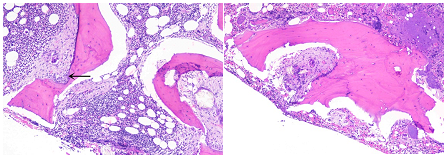

The inexplicable blood cell deficiency prompted a bone marrow aspiration and biopsy. There were many osteoblasts and osteoclasts close to bony trabeculae, along with localized trabecular resorption, in the bone marrow, which was found to be normocellular to slightly hypercellular. Additionally, there were areas of marrow fibrosis. Many needle-like, refractile crystals were grouped together in the marrow spaces, encircled by a massive cell reaction that is characteristic of a foreign body. These crystals exhibited strong birefringence when exposed to polarized light, which is consistent with the buildup of calcium oxalate (bone marrow oxalosis). The patient was diagnosed with Primary Hyperoxaluria with bone marrow oxalosis based on the patient's early-stage chronic kidney disease, long history of kidney stones, and unique bone marrow findings.

Figure 1: Bone trephine section shows hematopoietic areas surrounded by foreign body giant cells, fibrosis and also cartilage hypertrophy at ×40.